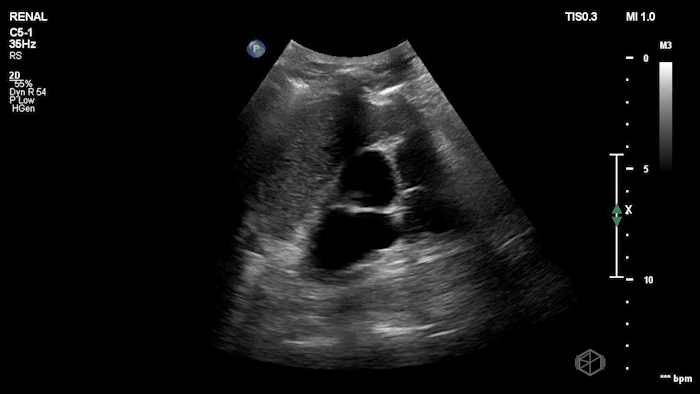

15 - What grade of hydronephrosis is this?

Severe hydronephrosis, cortical wall thinning is present.